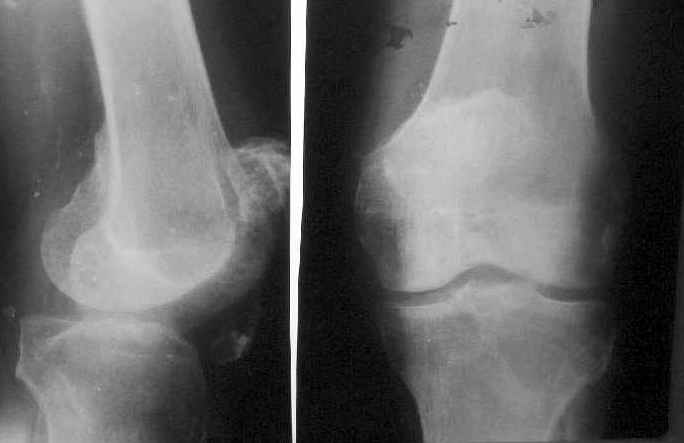

Пациент 53 лет травма 25.11.02. в салоне автомашины, получил множественные переломы ребер с ушибом легких и гемопневмотораксом, ротационно нестабильное повреждение таза: перелом боковых масс крестца, разрыв лонного сочленения, оскольчатый поперечный юкстатектальный перелом левой вертлужной впадины с центральным вывихом бедра и сегментарным переломом головки, перелом крыла правой подвздошной кости. Открытый многооскольчатый перелом костей правого предплечья, перелом правого бедра в нижней трети, перелом надколенника слева, перелом лодыжек левой голени с переломом заднего края левой большеберцовой кости подвывмхом стопы.Бедро срослось на вытяжении, лодыжки в гипсе, предплечье в аппарате. Под наше наблюдение попал 25.03.03. Выполнен чрескостный остеосинтез таза, с постепенной коррекцией положения отломков, затем 28.04.03 реконструкция вертлужной впадины для эндопротеза, синтез лонного сочленения. В настоящее время ходит с костылями, беспокоят боли в левом тазобедренном суставе, прогрессирует деформация головки. То есть в ближайших планах - эндопротезирование этого сустава. Однако смущает ряд моментов: В частности, на стороне предполагаемого эндопротезирования (левой) имеется разрыв собственной связки ниже надколенника, который подпаян к бедру (видно на фото сидя), то есть активного разгибания голени нет. А на правой стороне имеется штыкообразная деформация бедра, нет полного разгибания коленного сустава, хотя конечность опороспособна; ортопедическое укорочение 3 см.Вопросы: Что делать с левым надколенником и 4-главой мышцей? Восстанавливать ли ось и длину правого бедра? Если не трогать правое бедро, то на сколько компенсировать укорочение при эндопротезировании?